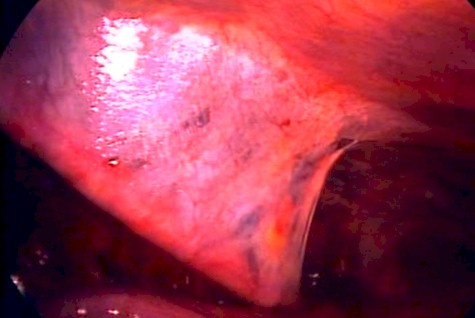

En el transoperatorio se visualizó lesiones de coloración pardusca con puntillados de color cerezo oscuro (Fig. 8 y 9).

Figura 8.

Figura 9.

Paciente de sexo femenino sin antecedentes patológicos respiratorios. Con recurrencia de neumotórax, y en las dos ocasiones en presencia del primer día del periodo menstrual. La sospecha se la comprueba en el transoperatorio de la videotoracoscopia, al encontrar lesiones no frecuentes y de coloración distinta; aunque sólo en un 30-50% de los casos se objetivan implantes en la pleura o en el diafragma durante el acto operatorio (3,10). No se tomo muestra de liquido pleural y fue posible estudiar el CA 125, mientras que el examen anatomopatológico de la pleura solo reveló células inflamatorias sin encontrar tejido endometrial. Se han comunicado muy pocos casos en los cuales la endometriosis pulmonar o pleural se demostrara histológicamente (12). Se mencionan como fuente primaria de las lesiones a la endometriosis torácica, que suele encontrarse asociada en un 20 % a 70 % de los casos (3,4), por lo cual se descarta las otras dos teorías de neumotórax catamenial. Por lo tanto recomendamos que en toda mujer fértil con neumotórax espontáneo deba hacerse una evaluación en relación con su ciclo menstrual. Y que el método preferido de investigación debe ser la videotoracoscopia por ser menos agresiva y por mejorar las opciones de visualización de lesiones anormales, ya sea en pleura o diafragma.